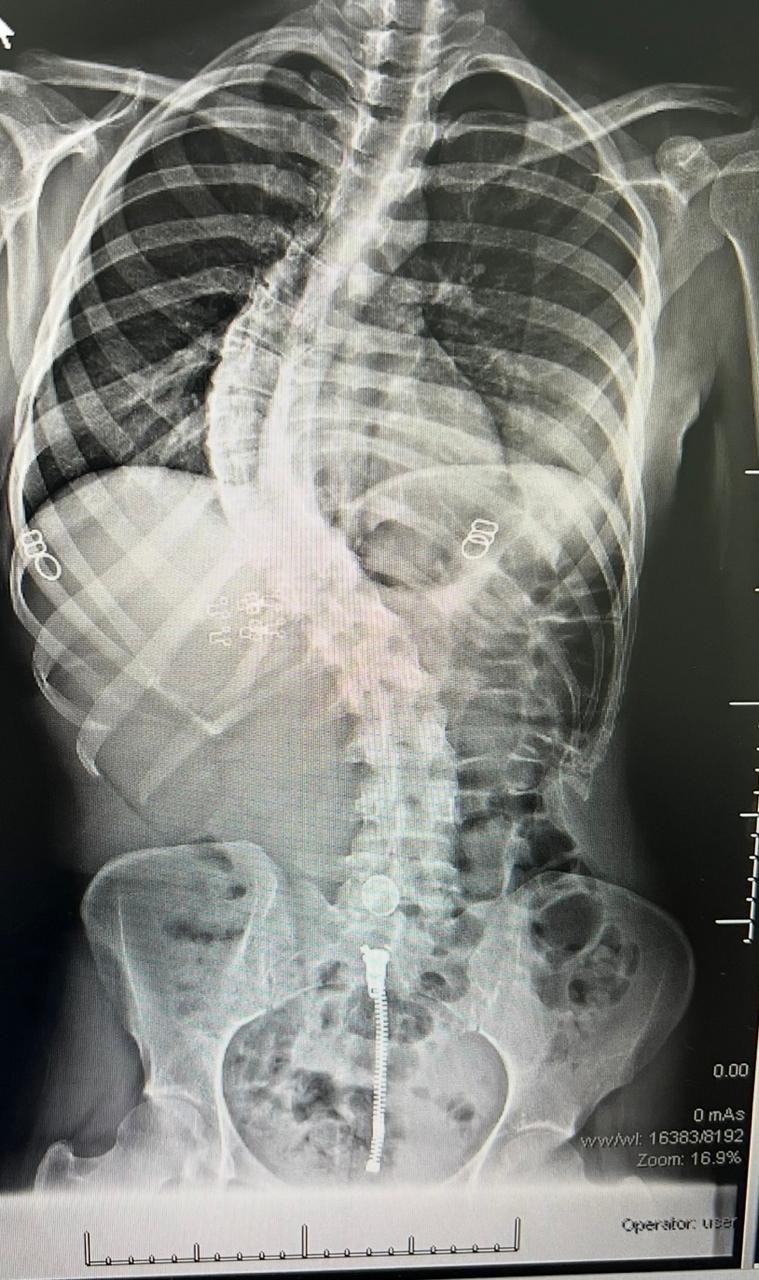

وخضعت الحالتان لتقييم طبي شامل ودقيق تضمن إجراء كافة الفحوصات الإكلينيكية والأشعة المتخصصة، التي كشفت عن وجود تشوهات ودرجات انحناء متقدمة استوجبت التدخل الجراحي العاجل لتفادي المضاعفات.

واستغرقت كل عملية نحو ثماني ساعات متواصلة من العمل الدقيق، نظراً لتعقيد الحالات وحاجتها لتنسيق عالٍ ولحظي بين جراحي العمود الفقري وفريق التخدير لضمان استقرار المريض.